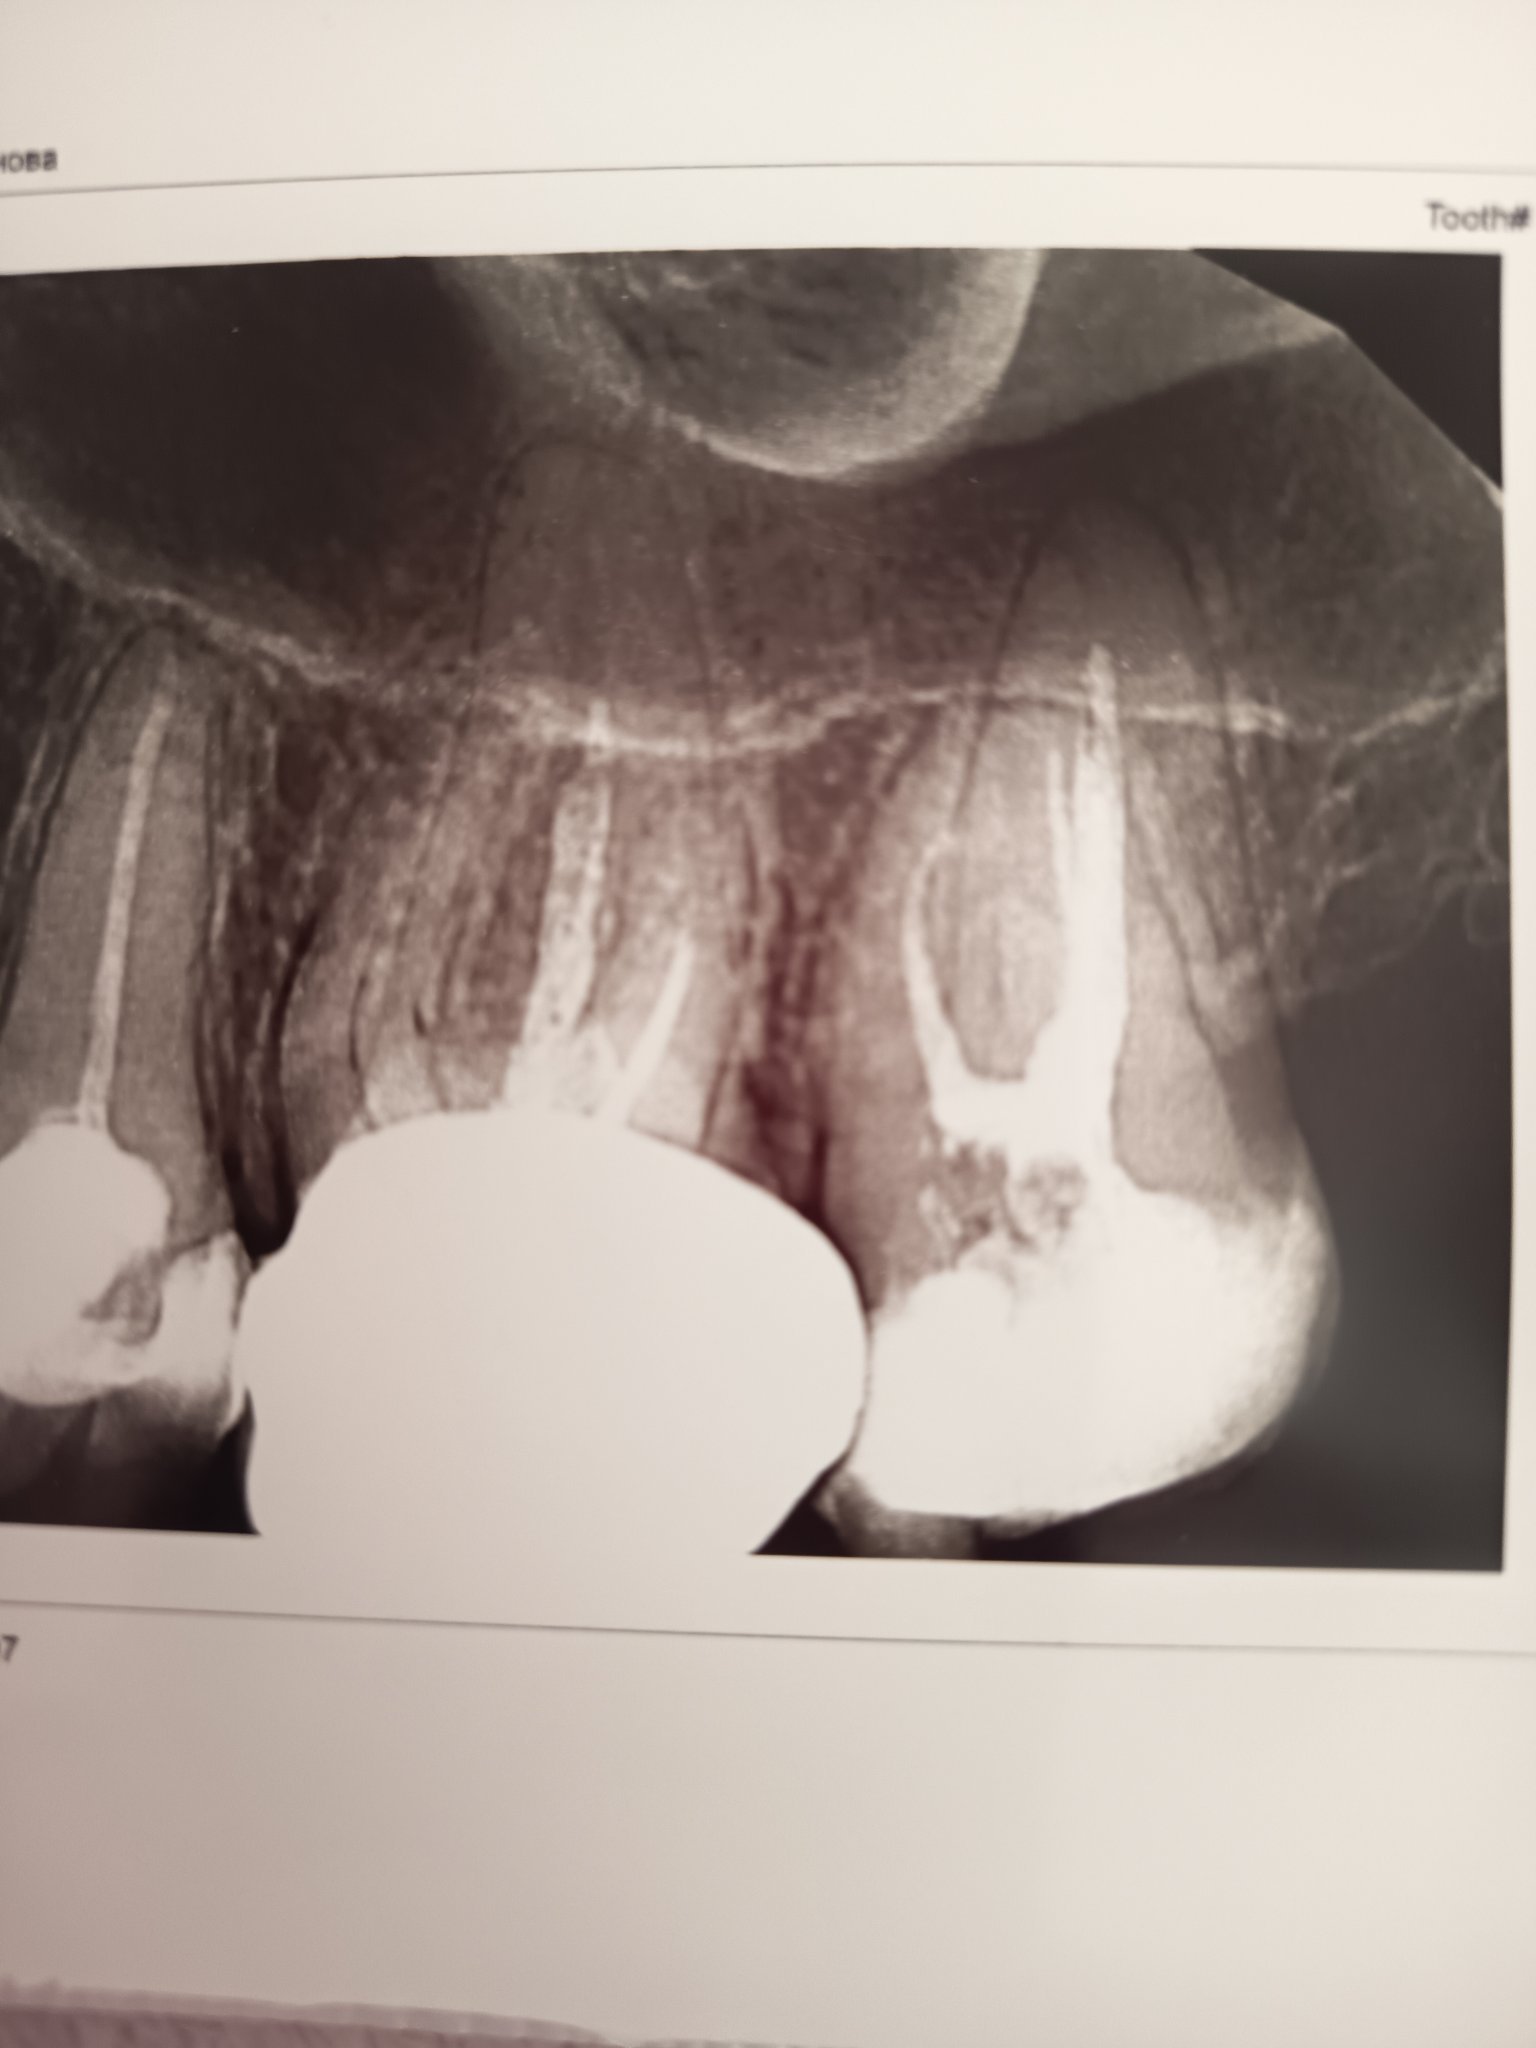

Основните разлики между базалните и конвенционалните импланти се крият в техния дизайн, метод на поставяне и ниво на надеждност. Базалните импланти са едночастови, предназначени за тотално обеззъбени пациенти и се поставят директно в костта. Те са лесни за поставяне и имат по-прост производствен процес, но могат да доведат до хронично възпаление и загуба на кост поради липсата на прецизни коронки. Конвенционалните импланти, от друга страна, се състоят от множество части и изискват множество етапи на лечение. Те предлагат по-голяма надеждност и възможност за точни коронки, което води до намалено възпаление и загуба на импланти.